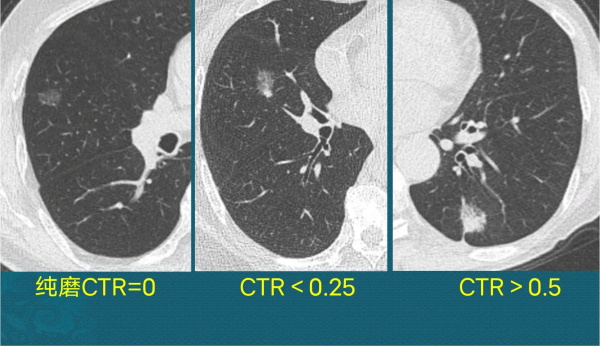

磨玻璃结节,是指直径<3 cm的局灶性密度增高影,密度可以不均匀。

上图三个都是磨玻璃结节,左图是纯磨,中图和右图是混合磨玻璃结节,这三位病人都是定期复查结节没有吸收,后来都做了微创手术切除,病理分别是原位癌、微浸润腺癌和浸润性肺腺癌。